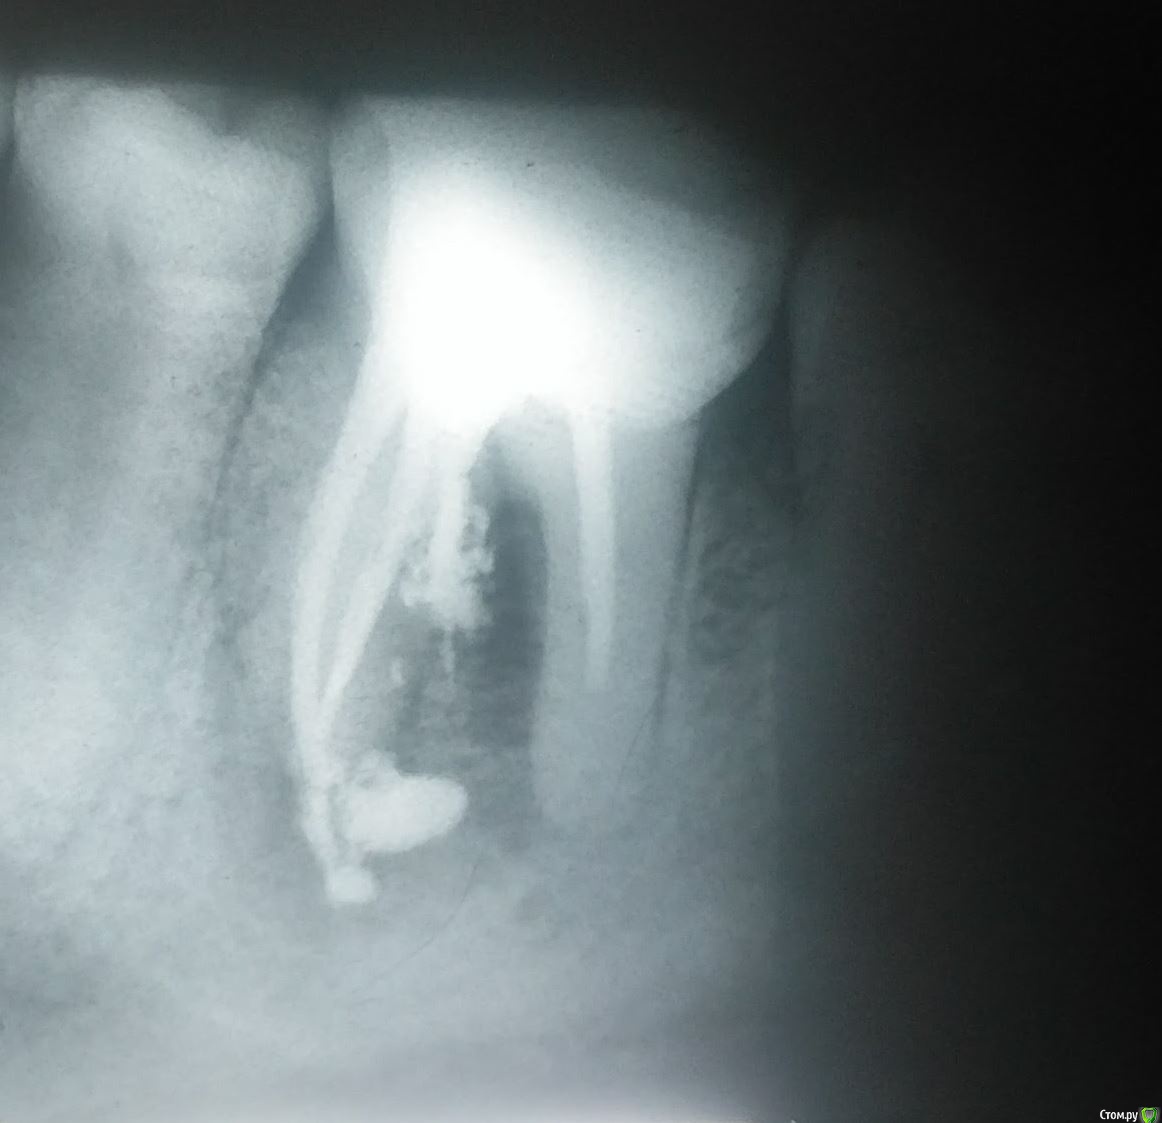

pru2009 Опубликовано 21 февраля, 2018 Поделиться Опубликовано 21 февраля, 2018 Три года тому назад были удалены нервы и установлена пломба на зуб и все было хорошо, но неделю тому назад стало болеть. При обследовании сказали что киста. Стоматолог предложил удаление зуба, но после просьб все-таки заложил лекарство для лечения кисты. Пару дней сильно болело, сейчас боль ушла, опухлость почти прошла, хотя и есть, предлагает на следующей неделе достать лекарство и запломбировать - потом под наблюдение для лечения. Сегодня делал рентген и консультировался с другим стоматологом, он категорически рекомендует удалять зуб и ставить имплант. Посмотрите снимки (это сегодня, лекарство все еще внутри зуба), какое ваше мнение стоит удалять или все-таки можно лечить? Просто жалко зуб удалять если можно вылечить. Ссылка на комментарий

pru2009 Опубликовано 23 февраля, 2018 Автор Поделиться Опубликовано 23 февраля, 2018 если перфорацию надежно закрыть, то еще постоит. Не будьте столь кровожадны )) Меня второй стоматолог напугал тем что на снимке видно что лекарство вытекло в десну, и это якобы ведет к повреждению кости, он меня вообще чуть ли не срочно отправлял на удаление зуба, только стоматолог-хирург к которому направили не взял телефон (видимо готовился к праздникам) поэтому я все еще с зубом.Но сейчас прочитал про перформацию - а получится ли ее закрыть, это ведь получится нужно сейчас убрать лекарство которое вытекло и закрыть канал так чтобы пломбирующий материл тоже не вытек, это без вскрытия десны и операции возможно ли? имею в виду только работая сверху зуба через каналы? или требуется какая-то специфическая операция? Ссылка на комментарий

St. Опубликовано 23 февраля, 2018 Поделиться Опубликовано 23 февраля, 2018 Удалять, закрытие перфорации не решит проблему воспаления между корнями. Если оставить ничего не делая может разболеться в любой неподходящий момент и тогда придется удалять по скорой 1 Ссылка на комментарий

Bier Опубликовано 26 февраля, 2018 Поделиться Опубликовано 26 февраля, 2018 лекарство жить не мешает, оно и рассосаться может постепенно.Если перфорацию надежно закрыть (если это возможно конечно) то и проблема "между корнями" заживет. Ссылка на комментарий